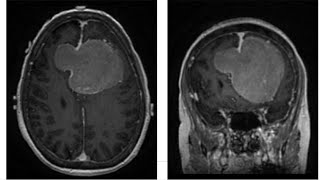

Left frontal craniotomy for resection of a gigantic parafalcine meningioma